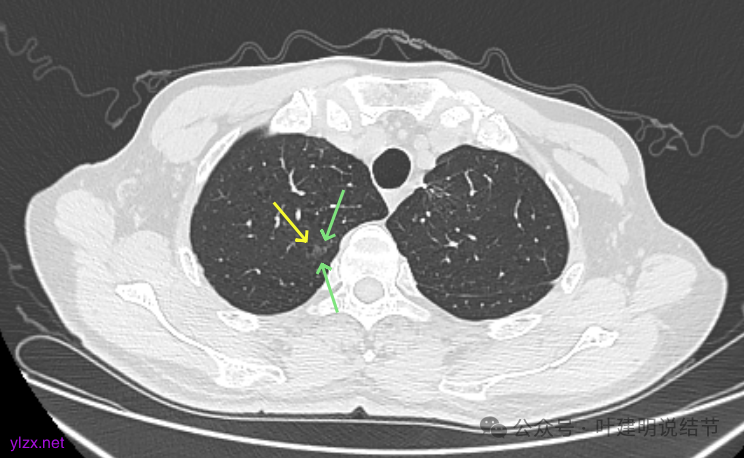

先看2020年9月的片子:

右上叶近脊柱旁有淡而纯的磨玻璃结节,整体轮廓与边界清楚,没有明显实性成分,也未见确切胸膜牵拉凹陷。

左上胸膜下有处偏长条小结节,也是磨玻璃密度的,轮廓较清。

左上叶前胸壁胸膜下有小结节,磨玻璃密度,有微小血管进入,轮廓与边界清。

左上叶混合密度结节,有毛刺与空泡征,瘤肺边界稍糊,灶内密度较为杂乱不均。